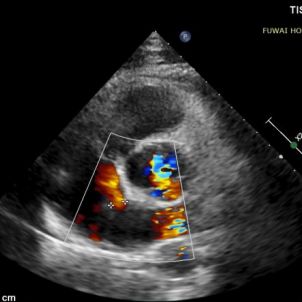

Compte tenu de la proximité du défaut à l'artère coronaire, un obturateur métallique traditionnel présentait un risque de compression, en particulier lors d'un effort physique. Un obturateur de TSA biodégradable (BDASD-I 18mm) a donc été choisi pour sa flexibilité, son risque moindre de blessure mécanique à long terme et sa capacité à se dégrader en dioxyde de carbone et en eau après avoir terminé la fonction de fermeture.

La procédure a été guidée par TTE suivant la procédure de PAN développée à l'hôpital de Fuwai. Cette technique d'imagerie en temps réel sans rayonnement offre une visualisation anatomique haute résolution, assurant un placement précis du dispositif et minimisant les complications-particulièrement utile chez les jeunes patients en âge de procréer.

1-day postoperative TTE revealed that the occluder is in good shape without residual shunt (see last figure).